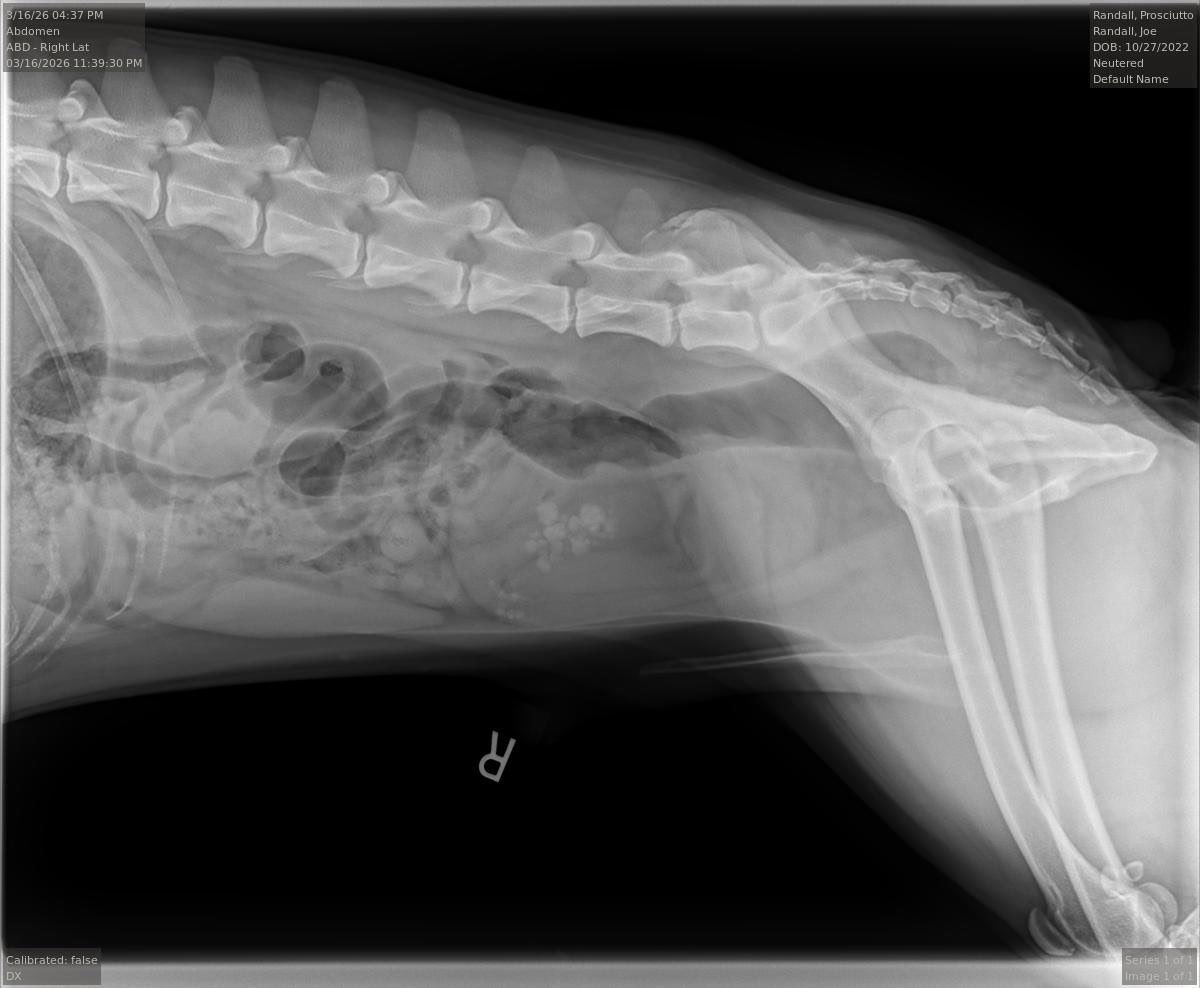

Update- emergent surgeries needed are cystotomy and perineal urethrostomy asap as the blockage was unable to be removed non surgically these and lifelong care and treatment are his only hope.

Today Prosciutto was diagnosed with bladder stones and a heart murmur when we took him in for a suspected UTI. After hours at his regular vet and with X-rays and testing, it was determined he has an active blockage and needs an immediate procedure to remove the blockage, followed by surgery as soon as possible for the many stones in his bladder. Otherwise, he will just become blocked again. He will also need a new specialized diet and to have more X-rays and treatment for his heart before they can safely put him under anesthesia for his surgery.